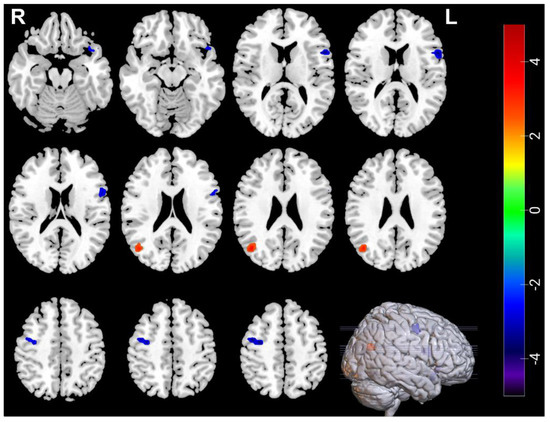

3.3. Neuroimaging Comparisons in MDDs Pre/Post-ECT

| Measures | Brain Regions | Voxel Size | Peak t Value | MNI Coordinates | ||

|---|---|---|---|---|---|---|

| Decreased | ||||||

| ALFF | Temporal_Pole_Sup_L | 30 | −4.0615 | −51 | 18 | −15 |

| ALFF | Frontal_Inf_Oper_L | 39 | −3.9169 | −54 | 12 | 12 |

| ALFF | Frontal_Mid_R | 34 | −4.2384 | 42 | −3 | 51 |

| Increased | ||||||

| ALFF | Occipital_Mid_R | 30 | 3.7765 | 42 | −66 | 24 |

| ReHo | Occipital_Mid_R | 46 | 4.5719 | 42 | −63 | 24 |

| ReHo | Temporal_Inf_L | 38 | 4.761 | −51 | −3 | −33 |